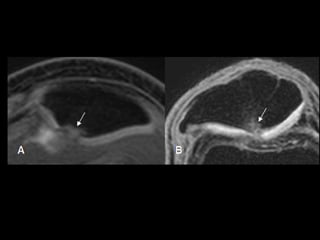

Menisco discoide

• Alteración congénita del desarrollo del menisco externo, es la

pérdida de la forma semilunar del menisco

• Esta anomalía los hace propensos a rotura

• El diagnóstico se realiza cuando se observa un menisco

marcadamente mayor que el menisco normal.